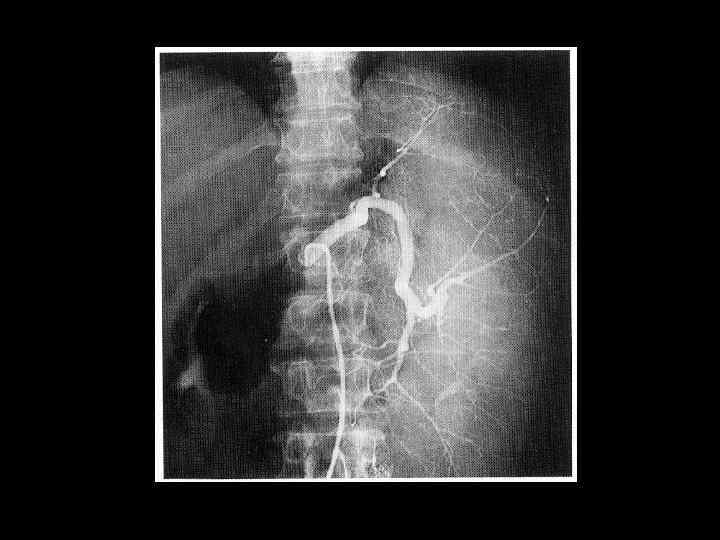

АКТУАЛЬНЫЕ ВОПРОСЫ РЕНТГЕНОЛОГИИ ЛУЧЕВАЯ ДИАГНОСТИКА ЗАБОЛЕВАНИЙ СЕЛЕЗЕНКИ Спленомегалия: Причины - Заболевания системы крови (гемолитические анемии, острые лейкозы, хронический миелоидный лейкоз, злокачественные лимфомы) - портальный цирроз печени - тромбоз селезеночной вены